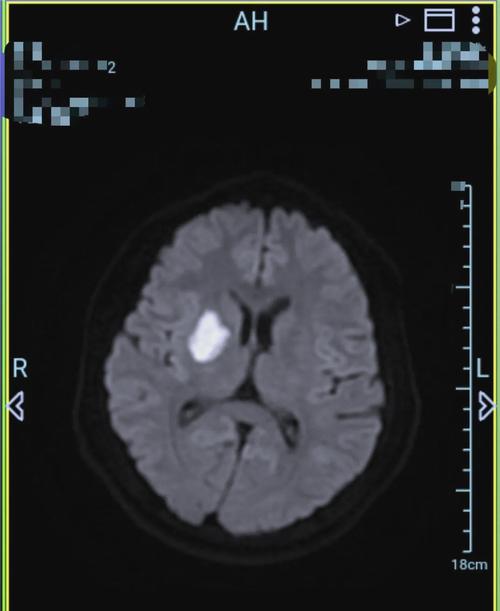

(图片来源网络,侵删)- 含义:这是“腔隙性脑梗死”的简称,这是一种缺血性脑卒中(也就是我们常说的“中风”或“脑梗塞”)的一种特殊类型。

- 形成原因:它不是大血管堵塞,而是由大脑深部穿通动脉的微小分支(直径通常小于2毫米)发生闭塞引起的,由于这些血管非常细小,堵塞后影响的脑组织范围也很小,会形成一个小的、空腔样的软化灶,所以被称为“腔隙性”梗死。

患者大脑右侧的基底节区域,发生了一个微小的血管堵塞,导致该区域的一小块脑组织缺血、坏死,形成了一个小软化灶(腔隙性梗死)。